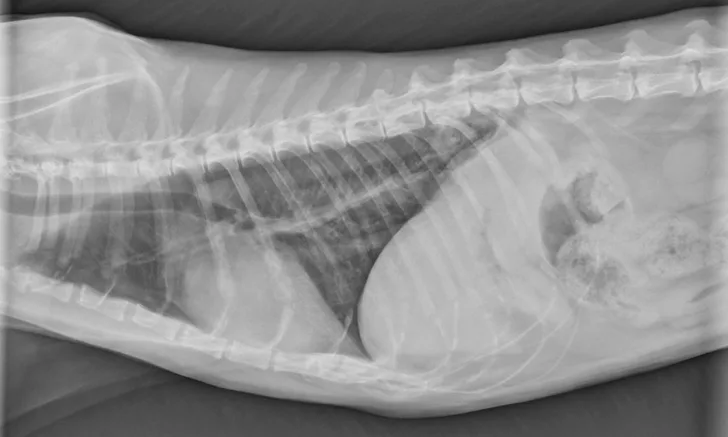

Figure 1

Lateral thoracic radiograph of a 14.5-year-old male domestic cat with a caudal dorsal cavity primary lung mass. Image courtesy of Rachel Moon, DVM, DACVR

Reported primary lung tumors (Figures 1 and 2) include squamous cell carcinoma and sarcoma, but adenocarcinomas are reportedly the most common histopathologic diagnosis.2 Adenocarcinomas are subcharacterized by location (ie, bronchial, bronchioloalveolar, alveolar) and grade. Carcinomas are graded on histopathology as differentiated or undifferentiated, with the grade directly correlating with metastatic incidence.1,3 Although most primary carcinomas are localized and solitary at diagnosis,1,4 the literature suggests that >50% of undifferentiated carcinomas and 90% of squamous cell carcinomas metastasize,1,3 with one study reporting ≈75% of feline lung tumors as metastatic.4 Metastasis to the lungs, skin, CNS, and digits may occur transpleurally, hematogenously, or via lymphatics or airways.1,3,4